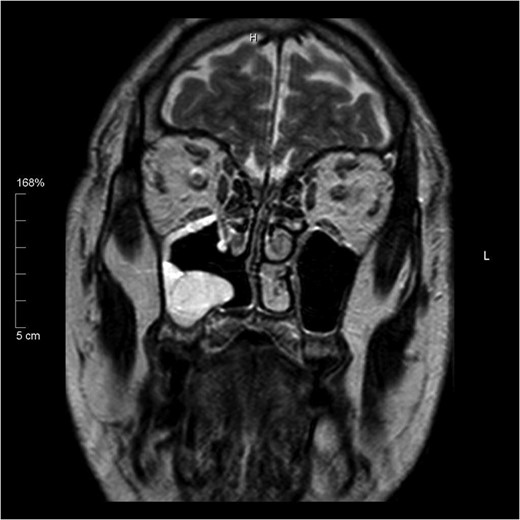

Histology of the mass confirmed sinonasal SDC. Tissue specimens showed cellular stroma extensively infiltrated by carcinoma composed of large eosinophilic cells with gland formation (Fig. 2). Widespread nuclear pleomorphism was evident. The sample was positive for cytokeratin-7 (CK7) (Fig. 3), epithelial membrane antigen (EMA), BerEP4 and demonstrated focal positivity for cytokeratin-5/6 (CK5/6). Post-operative MRI scans were requested to rule out residual disease or cervical lymphadenopathy (Fig. 4). Following review by Regional Head and Neck Cancer multi-disciplinary team and the oncologist, the patient was treated with a radical course of radiotherapy which was completed without complications. The patient has been reviewed regularly in the Head and Neck Cancer clinic with no evidence of recurrence at 18 months.

Coronal T2 image showing post-operative changes. No evidence of residual tumour.